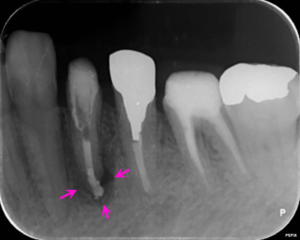

左下6番の歯の根の中に折れている器具(矢印赤)があり、前医ではこれ以上根管治療が不能とのことでした。また、病変のある左下4番の歯の根管治療も提案し、患者様の合意を頂き治療をすすめることになりました。

左図のレントゲン写真では左下4番の歯の根の先に炎症があり骨が溶けている部分があります(矢印ピンク) 。

左下6番の歯の根の中の折れている器具を除去した後のレントゲン写真です。矢印赤のところにあった器具が除去されていることがわかります。